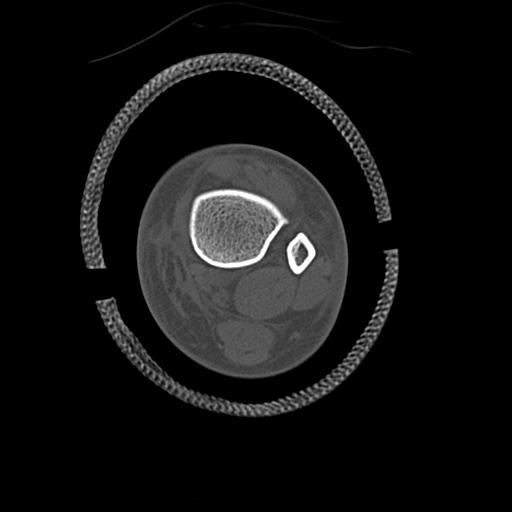

49554 3/13 膝 4R 3/16 4R 1/18 2R 78歳男性 膝蓋骨骨折